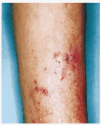

Mujer de 58 años, sin antecedentes patológicos de interés, que consultó por unas lesiones papulosas y nodulares eritematosas en cara anterior de pierna derecha, con ocasional supuración y de aparición progresiva. Este cuadro había comenzado unos 9 meses antes con una lesión nodular eritematosa única que se fue extendiendo, apareciendo en las semanas posteriores nuevas lesiones a lo largo de la pierna de forma ascendente, en disposicion esporotricoide, dejando zonas de piel sana entre ellas (Fig. 1). No existía dolor ni prurito y no se palpaban adenopatías. En la anamnesis destacaba el antecedente de herida traumática 1 año antes de la aparición de las lesiones con una hamaca de playa.

FIG. 1.--Lesiones papuloeritematosas y ulcerocostrosas confluentes en cara anterior de pierna derecha en disposición lineal ascendente.